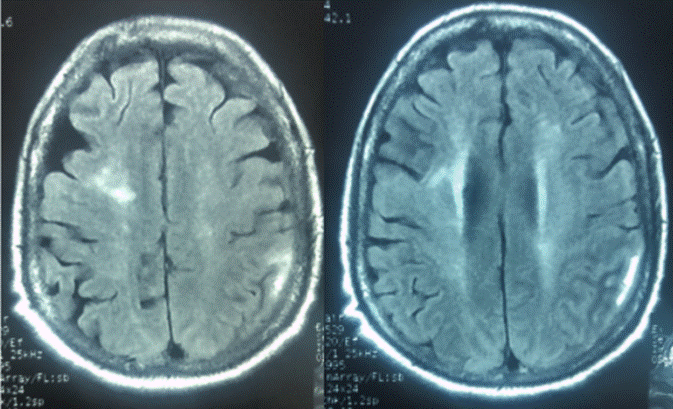

De igual forma, al ingreso a urgencias se inició infusión intravenosa con nitroprusiato de sodio, gracias a lo cual las cifras tensionales se redujeron de forma ligera. Luego de esto, la paciente fue remitida al servicio de medicina interna, a cargo de nefrología y neurología, donde se ordenó tomografía simple de cráneo que resultó normal, así como análisis de urea que se encontró en 95 y creatinina que fue de 8.6 md/dL; los niveles electrolitos se hallaron normales. Luego de la estabilización hemodinámica y neurológica se indicó resonancia magnética nuclear simple de cráneo donde se observaron múltiples imágenes hiperintensas en sustancia blanca subcortical y en región cortical parieto-occipital izquierda compatibles con PRES (Figura 1).

Fuente: documento obtenido durante la realización del estudio

Figura 1 Resonancia magnética simple de cráneo secuencia FLAIR.